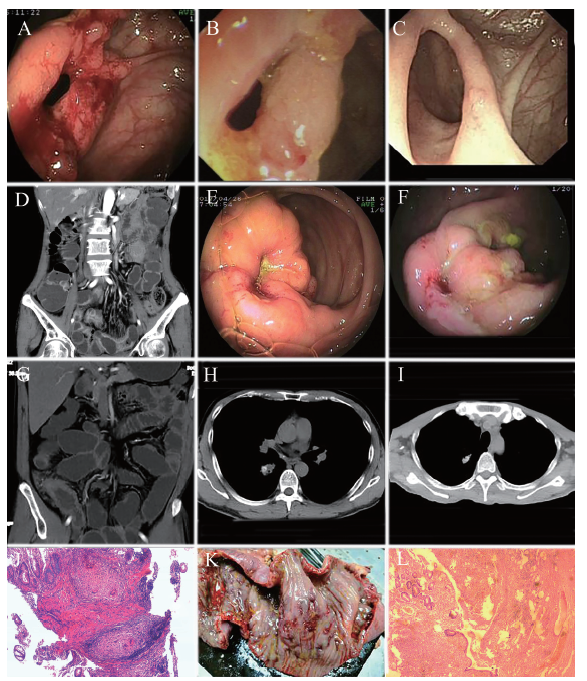

例2 患者男,46岁。因反复腹痛、大便不规则伴消瘦半年,加重半个月于2017年4月25日入院。入院体格检查:消瘦面容,心、肺听诊无异常,腹部稍膨隆,未见胃肠型及蠕动波,腹肌稍紧张,右中下腹部压痛,无反跳痛,墨菲征阴性,肝、脾肋下未触及,腹水征阴性,肠鸣音6 ~ 8次/分,双下肢无水肿。尿常规、肝肾功能、电解质、血糖、ESR、癌胚抗原、糖类抗原199、凝血功能、心电图均未见异常。HBsAg、HBeAb、HBcAb、结核抗体、HIV抗体均阴性,痰未找到结核杆菌。血常规示白细胞14.04×109/L、中性粒细胞0.89、血小板400×109/L;CRP 2.61 mg/dl。粪便常规隐血阳性。腹部X线立位片示不完全性肠梗阻,胃镜示非萎缩性胃炎伴糜烂,肠镜示回盲瓣及部分回肠溃疡性质待定,病理活检(回盲部黏膜)黏膜中度慢性炎症,腺上皮轻度非典型增生,伴炎性坏死。超声内镜示回盲瓣溃疡并狭窄,病理活检(回盲部)肉芽肿性炎症,结核可能性大;TB-IGRA检测(+)、T-N的值为121.4 pg/ml。胸部CT示右肺感染性病变,考虑继发性肺结核。全腹部CT示回肠末端炎性病变并腹腔淋巴结肿大。拟诊为回盲部结核并不完全性肠梗阻、右肺继发性肺结核,给予异烟肼+利福喷丁+盐酸乙胺丁醇三联抗结核、营养支持等处理,症状好转出院。患者于2017年6月、7月出现腹痛加重,伴肛门排气排便减少、恶心、呕吐,入院查粪便常规示隐血阳性。血常规、尿常规、肝肾功能、电解质、CRP均无明显异常。结核抗体阴性,ESR 25 mm/h;肠镜示回盲部溃疡并变形、狭窄、结肠多发性息肉,予肠镜下回盲瓣狭窄球囊扩张治疗及抗结核、抗感染等处理,症状逐渐好转出院。2017年9月第4次入院,血常规示血红蛋白104 g/L、血小板490×109/L;粪便常规示隐血阳性;ESR 70 mm/h,CRP 2.63 mg/dl;尿常规、肝肾功能、电解质、血糖、癌胚抗原、糖类抗原199均未见明显异常。胸部CT示右肺感染性病变,考虑继发性肺结核。对比4月的CT片,肺内病灶较前吸收、减少。全腹部CT提示回肠末段管壁增厚,管腔狭窄,继发肠梗阻。肠镜示回盲瓣溃疡并狭窄(较前好转)、结肠多发性息肉,病理活检示(回盲部)管状腺瘤伴低级别上皮内瘤变,未见结核征象。治疗上继续予三联抗结核及营养支持处理,患者仍有不完全性肠梗阻,有外科手术指征,建议采用外科手术治疗,患者拒绝。出院后一直服用三联抗结核治疗,于2018年1月、8月多次因高热入院,血常规示白细胞11.51×109/L、中性粒细胞0.80、血小板496×109/L;粪便常规隐血阳性;CRP 13.40 mg/dl;ESR 59 mm/h;其余实验室检查无明显异常。胸部CT示右肺继发性肺结核;肠镜示回盲瓣及周围溃疡性质待查:结核?克罗恩病?病理活检示(回盲瓣)溃疡病变。全腹部CT及CT小肠成像示:①第5组小肠及盲肠、升结肠改变,肠系膜区淋巴结增大,木梳征不明显,考虑为肠结核并不完全性肠梗阻;②腹主动脉局限性慢性腹壁血栓形成,最厚处约10 mm,管腔狭窄约50%。仍考虑肠结核并回盲瓣狭窄伴不完全性肠梗阻、右肺继发性肺结核,请感染科及普外科会诊,建议继续予抗结核治疗,必要时行外科手术治疗。继续给予抗结核治疗后患者再次出现发热10 d,于2019年11月5日第7次入院,血常规示白细胞13.40×109/L、中性粒细胞0.82、血小板533×109/L;肝功能示总蛋白55.4 g/L、白蛋白30.8 g/L;CRP 12.50 mg/dl,ESR 48 mm/h。结核抗体弱阳性。血培养无细菌及真菌生长,痰未找到结核杆菌。腹部X线立位片示不完全性肠梗阻。胸部CT示右肺继发性肺结核,对比8月的CT结果,肺内病灶吸收缩小、钙化。全腹部CT示腹部肠管壁广泛增厚并肠梗阻,肠系膜区淋巴结增大。肠镜示回盲部溃疡并回盲瓣狭窄,考虑结核可能。回盲部息肉病理活检示(回盲瓣)送检黏膜慢性活动性炎症,未见结核病变。患者给予正规抗结核治疗后,仍反复出现肠梗阻,有外科手术指征,遂于2019年12月13日在全身麻下接受剖腹探查+远端回肠部分切除+回盲部切除术。术中见肝、胆、胰、脾、胃、盆腔等未见明显异常;回盲部呈瘢痕改变,回盲瓣口处明显狭窄,小指头难以通过,远端回肠明显扩张,从回盲部至远端回肠约110 cm肠壁呈明显增厚及多处团块状瘢痕样改变,质较硬,局部肠系膜及肠系膜根部淋巴结明显增大,质较硬,最大者约大拇指大小,近端空肠未见明显异常,术后病理活检示:①(回肠)送检肠壁全长呈铺路石样水肿改变,镜下见多个深在型裂隙样溃疡,肠壁全层慢性炎症,肠系膜多个淋巴结反应性增生,符合克罗恩病表现;②慢性阑尾炎。最后诊断为克罗恩病(回结肠型、狭窄型、活动期,轻-中度)、右肺继发性结核,术后予以抗感染、抑酸护胃、肠内营养(安素)等处理,复查血常规及血液生化示血红蛋白73 g/L、红细胞2.40×1012/L、白细胞9.14×109/L、中性粒细胞0.74、血小板96×109/L;白蛋白37.7 g/L,CRP 2.64 mg/dl。患者症状好转出院,继续服用安素,建议其半个月内至消化内科复诊。随访至撰稿日(2019年12月30日),患者病情平稳。病例2相关图片见图1E ~ L。

图1 两例酷似肠结核的克罗恩病患者相关检查图

A:病例1治疗前回盲瓣内镜图;B:病例1 抗结核治疗3个月后回盲瓣内镜图;C:病例1 免疫抑制治疗后回盲瓣内镜图;D:病例1 CT小肠成像提示小肠节段性狭窄与扩张,典型的木梳征;E:病例2治疗前回盲瓣内镜图;F:病例2抗结核治疗3个月后回盲瓣内镜图;G:病例2术前CT小肠成像显示回盲瓣情况;H:病例2术前右侧胸部CT;I:病例2抗结核治疗1年后右侧胸部CT;J:病例2内镜病理活检提示肉芽肿性炎症,结核可能性大(HE染色,×40);K:病例2手术大体标本提示病变肠道呈铺路石样改变,多处不规则溃疡;L:病例2大体组织病理活检示肠壁全长呈铺路石样水肿改变,镜下见多个深在型裂隙样溃疡,肠壁全层慢性炎症,肠系膜多个淋巴结反应性增生(HE染色,×40)